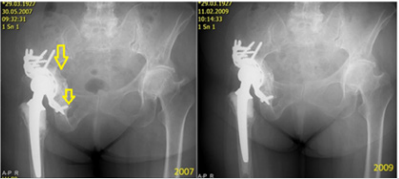

In our institution, 549 hips were re-implanted in the 4-year period from 2003 to 2007, with 243 of those re-implantations involving an acetabular component. BS plate was used in 78 (28.8%) of those latter cases, with only 8 of the patients being lost to follow-up. Also, in our institution, since 2000, we have preferred to perform non-cemented total hip replacements (THRs) in younger patients (under 70 years-old), and we have noted the need to perform re-implantation for subsequent defects, which tend to be larger, and especially so with the acetabular component (Figure 4). All patients with BS plate re-implantation were assessed by x-ray of the pelvis to identify cases of asymptomatic loosening; only 5 cases (7%) were found. In follow-up, the patients were re-operated (two times in total for 4.2% of the cases to address complete loosening or for an infectious complication in 2 cases (2.8%), with one needing full extraction of the BS plate. (Figure 5) provides an excellent representation of a case of the BS plate loosening itself.

Figure 5: Representative case of mechanical loosening of the BS plate. The proximal screws were fixed into defective bone, and a final revision was made by implantation of a hemispheric acetabular modulus. The final panel shows the results of the re-reimplantation (occurred and imaged in 2012).

The migration occurred proximally, with breakage of the proximal screws and migration of the plate (from 2009). Then, a mixture of the screws is seen in the bottom of the joint space (2010) and luxation (2012). In the same year (2012), we re-admitted the patient for re-reimplantation and implanted a hemispheric modulus with excenter and larger revision stem. In Figure 6, a case of mechanical loosening of the BS plate is presented. This event does not, generally, lead to positional plate loosening. Instead, the plate protrudes into the pelvis slightly, though it is still capable of full-weight bearing.